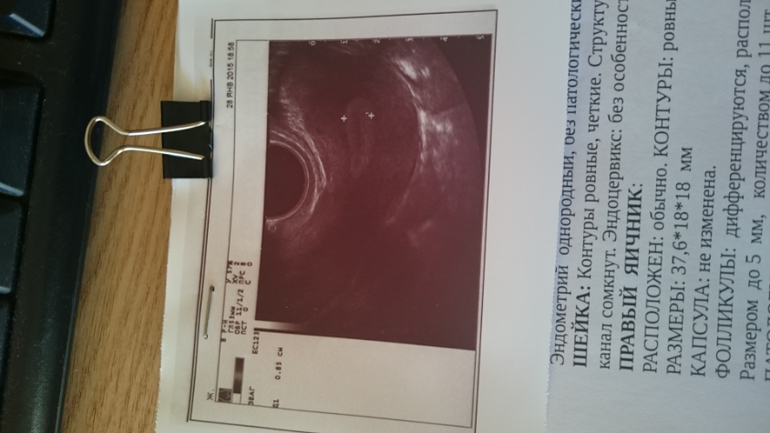

Но за весь этот месяц таки есть один положительный момент - эндик явно стал лучше, нет ячеистой структуры теперь))

Вот так, фото последнего УЗИ и анализов прилагаю)